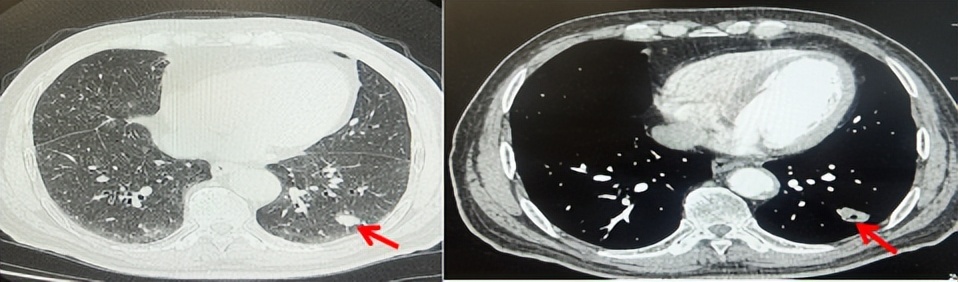

71岁男性,高血压病史20年,口服药物治疗,无糖尿病、心脏病等基础疾病,吸烟史50年,20支/天,已戒1年余,无饮酒史,无肿瘤家族史。2023.11因咳嗽、咳痰行胸CT检查:左肺下叶占位性病变,大小约12mmx8mm(如图5)。2023.11.20行“单孔胸腔镜左肺中下叶切除、肺门及纵隔淋巴结清扫、胸膜粘连松解术”;术后病理:(左肺下叶)结合免疫组化鳞状细胞癌(中、低分化),局部见脉管内癌栓,未见确切神经侵犯,(气管切缘)净。(淋巴结)未见转移癌0/19(4组0/1;5组0/1;6组0/2;7组0/1;9组0/1;10组0/2;11组0/3;12组0/2;13组0/2;14组0/4)。术后分期pT1bN0M0 IA期,术后定期复查。

2024.09.12复查胸部CT示左侧胸膜结节,大者约为27mmx13mm,考虑转移可能性大,纵隔淋巴结增大,恶性?(如图6)。患者行胸膜穿刺活检取病理,结果示(胸膜)结合免疫组化,支持鳞状细胞癌,PD-L1(克隆号28-8)TPS约20%。分期为rT0N2bM1a IVA期,DFS为10个月。2024.09.24起行替雷利珠单抗联合紫杉醇+卡铂方案治疗4周期,复查胸CT评效SD(如图7)。后患者因脑梗塞停止治疗,于综合医院就诊,后未返院复查及治疗。

图5:患者手术前(2023.11)胸部CT肺窗及纵隔窗

图6:患者胸膜及纵隔转移(2024.09)胸部CT肺窗及纵隔窗

图7:替雷利珠单抗联合白蛋白紫杉醇+卡铂治疗4周期后(2024.12)胸部CT肺窗及纵隔窗